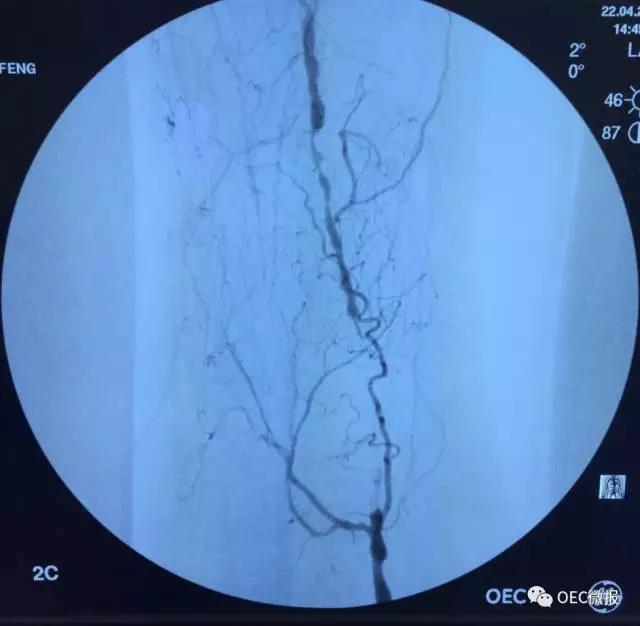

从颈动脉成形术,到股动脉血栓切除;从主动脉瘤支架置入,再到髂动脉闭塞再通。OEC 9900像操控它术者一样,无所不能,使得参会者兴趣盎然。介入治疗和外科手术在两个手术间同时直播进行。介入手术的便捷、高效显露无遗。有人说中C只能用于小医院,大医院都要用大C,而我们用实践证明,没有最好的设备,只有最适合你的OEC!